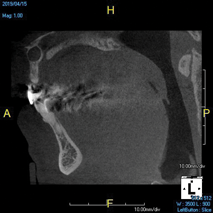

(10.) Tooth No. 31 in this 14-year-old patient does not exhibit caries. It is a “ghost tooth.” The lack of a periapical pathosis, the location of the tooth relative to the inferior alveolar nerve, and the development of tooth No. 32 are all visible in the CBCT image. These factors will aid the clinicians in developing a treatment plan to deal with this unusual internal resorption case.

Figure 10